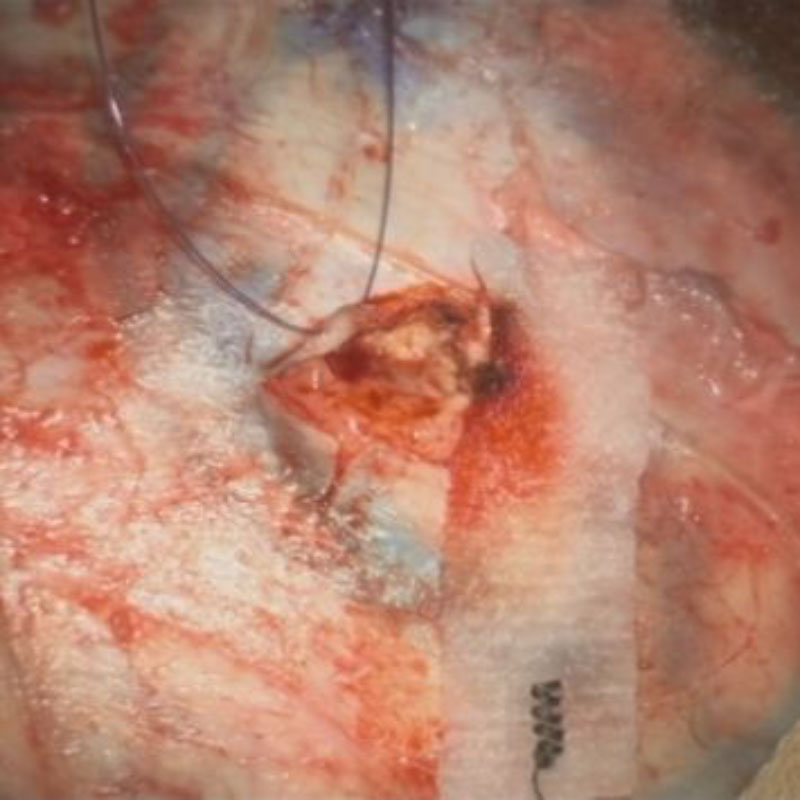

676

'25年10月

20代

脳幹部腫瘍

頭蓋内腫瘍摘出術

No.’25_78 摘出 前

No.’25_78  摘出 中

No.’25_78 摘出 後